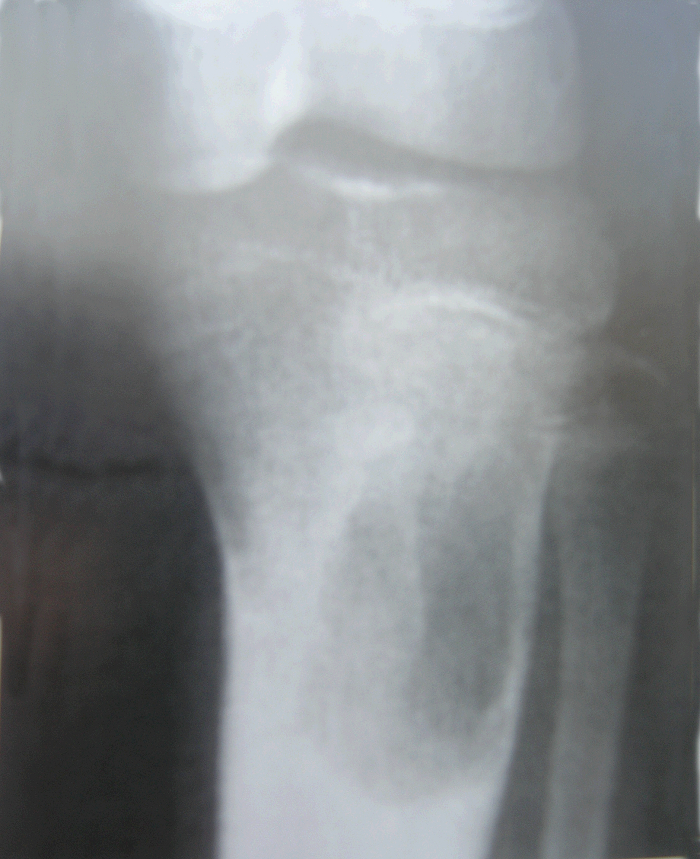

患者 男 15岁 左胫骨近段软骨粘液样纤维瘤

图 1 术前X线片

a:正位 b:侧位

典型X线表现为长骨干骺端圆形或椭圆形溶骨性破坏,常有斑点状钙化,呈偏心性,骨皮质膨胀变薄,病损长轴与病骨长轴平行,病灶边缘清晰,周围可见反应性硬化带。肿瘤内部有时出现的粗细不等的骨性间隔,类似于骨小梁,系因肿瘤呈分叶状生长,骨皮质膨胀性破坏不均匀所致,又称为“假性骨小梁形成”。